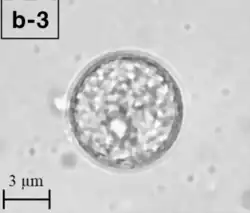

| A Balamuthia mandrillaris cyst | |

B. mandrillaris is a free-living, heterotrophic amoeba, consisting of a standard complement of organelles surrounded by a three-layered cell wall (thought to be made of cellulose or a similar polysaccharide[8]), and with an abnormally large cell nucleus. On average, a Balamuthia trophozoite is about 30 to 120 μm in diameter. The cysts fall around this range, as well.[9]

Balamuthia's lifecycle, like the Acanthamoeba, consists of a cystic stage and a non-flagellated trophozoite stage, both of which are infectious, and both of which can be identified in the brain tissue on microscopic examination of brain biopsies performed on infected individuals. The trophozoite is pleomorphic and uninucleated, but binucleated forms are occasionally seen. Cysts are also uninucleated, possessing three walls: an outer thin irregular ectocyst, an inner thick endocyst, and a middle amorphous fibrillar mesocyst.[10]